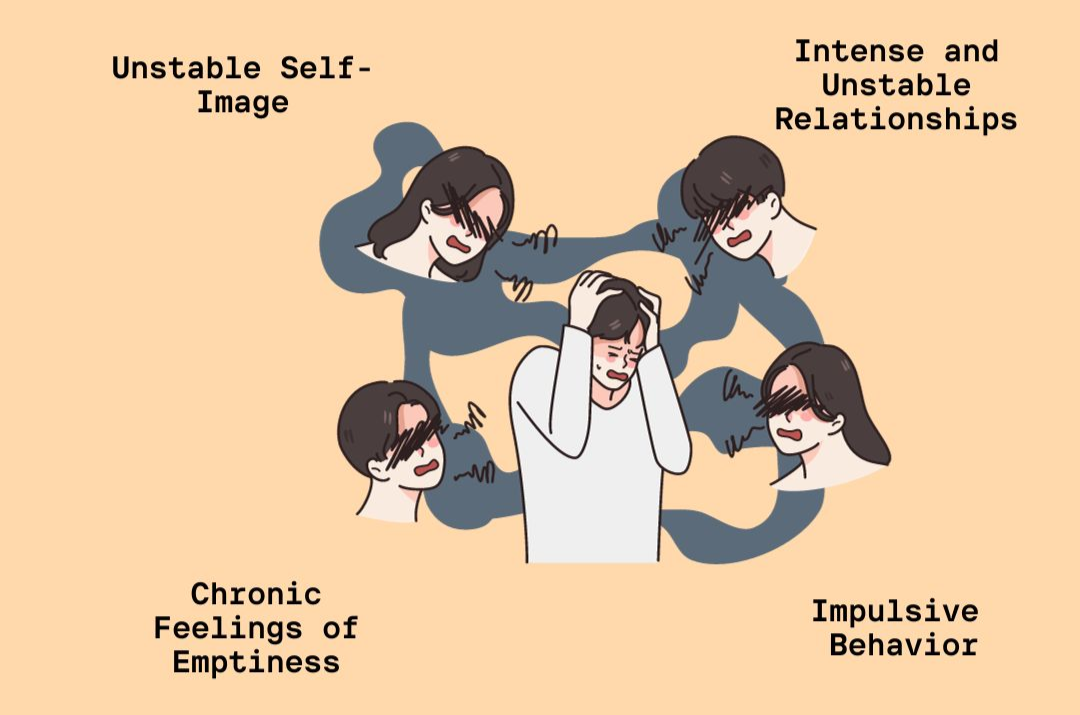

Disorders refer to abnormal conditions affecting physical or mental health, disrupting normal functioning. They can range from physical ailments like heart disease to psychological issues like anxiety. These conditions may be caused by genetics, environment, or lifestyle. Diagnosis often involves medical exams and tests. Treatment can include therapy, medication, or lifestyle changes to improve quality of life.

Disorders refer to abnormal conditions affecting physical or mental health, disrupting normal functioning. They can range from physical ailments like heart disease to psychological issues like anxiety. These conditions may be caused by genetics, environment, or lifestyle. Diagnosis often involves medical exams and tests. Treatment can include therapy, medication, or lifestyle changes to improve quality of life.